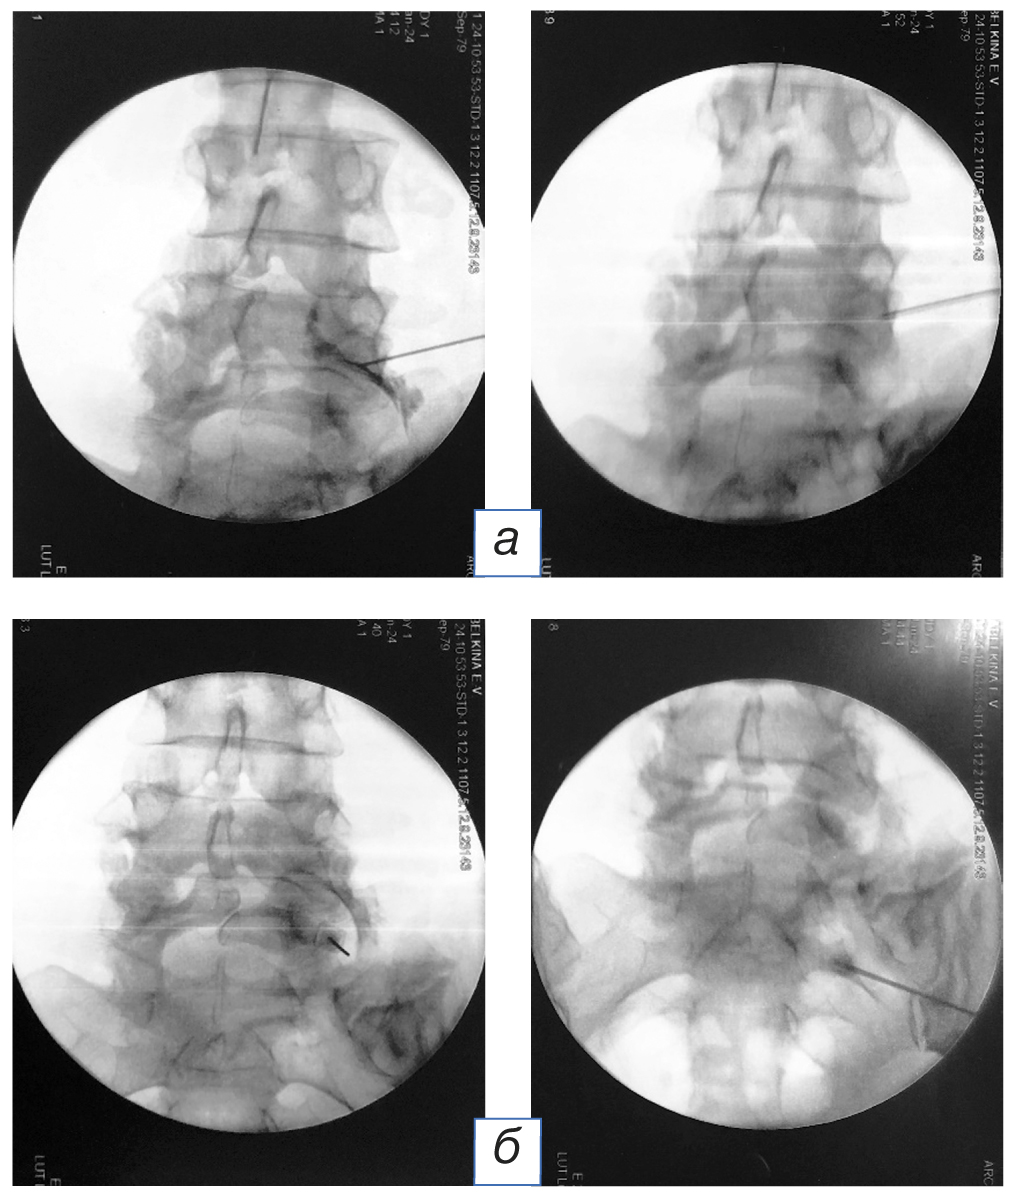

Проведено оперативное лечение (24.01.2024) — импульсная радиочастотная абляция дорзального ганглия и корешкового нерва на уровне фораминальных отверстий LIV–LV справа и термальная радиочастотная абляция возвратного нерва Люшка на уровне LIV–LV и LV–SI справа.

Хирургическое вмешательство. В положении больного на животе проведена местная инфильтрационная анестезия раствором ропивакаина 5 мг/мл в объеме 10 мл, отступя 10 см от средней линии на уровне LIV–LV тел позвонков из бокового доступа с проколом кожи и подлежащих мягких тканей. Под контролем электронно-оптического преобразователя в стерильном поле через прямую канюлю с острым кончиком проведён активный электрод с мандреном и тефлоновой изоляцией длиной 200 мм, диаметром 20 G, активным кончиком 10 мм к зоне деструкции (область нижнего треугольника межпозвонкового отверстия LIV–LV справа, образованного дугоотростчатыми суставами в месте прохождения корешкового нерва). Контроль расположения конца канюли с помощью контрастирования (1 мл йогексола 300). Введён электрод из термопары для проведения сенсорной и моторной стимуляции. Импедансометрия — диапазон составил 220–230 Ом. Проведено импульсное радиочастотное воздействие в режиме нейромодуляции с использованием генератора Cosman G4 при 42°C в течение 120 секунд (вверх и медиально, затем вниз и медиально, чтобы увеличить размер воздействия на дорсальный ганглий корешка DRG). Электрод и игла удалены. Далее последовательно выполнена термальная радиочастотная абляция (деструкция) возвратного нерва Люшка (при температуре 90° в течение 1,5 минут) под контролем электронно-оптического преобразователя в проекции точки scotty dog на уровне дугоотросчатого сустава LIV–LV и LV–SI справа под местной инфильтрационной анестезией [14, 16]. Электрод и игла удалены. Асептическая повязка. Продолжительность операции 35 минут. Кровопотери нет (рис. 3).

Рис. 3. Интраоперационные рентгенограммы: электрод установлен на уровне дорзального ганглия и корешкового нерва в проекции фораминального отверстия LIV–LV справа с целью верификации корешка и правильного положения иглы; контрастирован йогексолом 300 корешок и проведена импульсная радиочастотная абляция (а); электрод установлен в проекции дугоотросчатого сустава LIV–LV и LV–SI справа в проекции нерва Люшка, иннервирующего фасеточный сустав, для проведения термической радиочастотной абляции (б) [16]

Fig. 3. Intraoperative radiographs: the electrode is installed at the level of the dorsal ganglion and radicular nerve in the projection of the LIV–LV foramen on the right, to verify the root, contrast with iohexol 300 was performed to perform pulsed radiofrequency ablation (а); the electrode is installed in the projection of the facet joint LIV–LV and LV–SI on the right in the projection of the Luschka nerve innervating the facet joint for thermal radiofrequency ablation (б) [16]